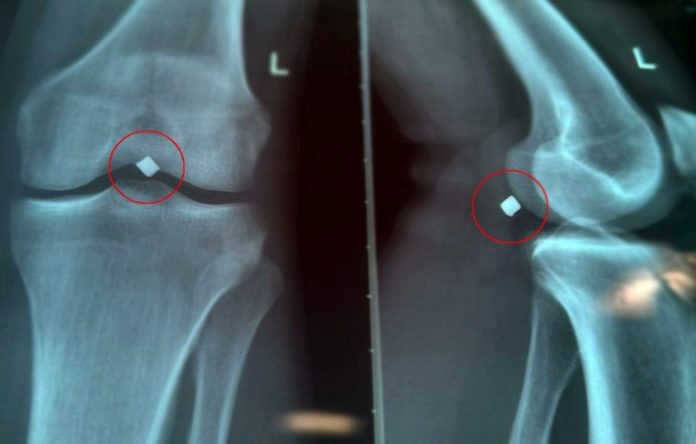

«Провели обследование, рентген показал местонахождение осколка. Во время вмешательства выяснилось, что осколок лежал прямо на стенке подколенной вены и практически пролабировал ее, создавая прямую угрозу жизнеугрожающего кровотечения. Работа хирургов требовала ювелирной точности. Операция прошла успешно, осколок был благополучно и аккуратно удален», — рассказал к.м.н., врач сердечно-сосудистый хирург Карпов Вячеслав Владимирович.